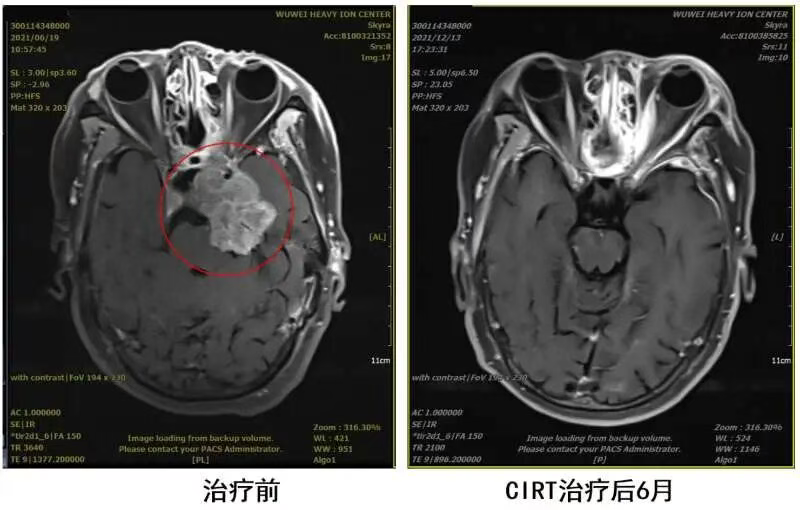

Auntie Qiao found a second treatment option for chordoma: carbon ion radiotherapy. Recommended by fellow patients, Auntie Qiao came to our hospital and received carbon ion therapy, with a total local tumor dose of 57Gy (RBE). After carbon ion therapy, symptoms such as facial paralysis, limited movement of the left eyeball, and mouth corner deviation improved compared to before. She remarked with emotion: "If only I had known about this radiotherapy treatment after my first surgery, the situation might be better than now. If only I had come to your hospital earlier." Now, Auntie Qiao undergoes an MRI check every 6 months. The mass has significantly reduced in size compared to before, and her quality of life has also improved markedly. During the National Day holiday, Auntie Qiao traveled to Gansu. When she came to visit us, the movement of her eyeballs was no longer restricted, the gloom in her eyes had vanished, replaced by unconcealable joy.

Due to the special location of skull base chordomas, they often invade and compress the brainstem. Auntie Qiao's lesion protruded into the pons. Conventional photon radiotherapy and similar methods cannot protect the brainstem, whereas heavy ions have unique physical advantages enabling precise "targeting" of the tumor. The biological advantages of heavy ions have a good effect on radiation-resistant tumors like chordomas. Auntie Qiao's skull base chordoma with brainstem compression has been "cured."